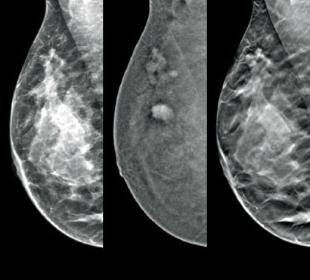

Hologic is transforming breast care. We apply cutting-edge science to accelerate discovery, improve efficiency and continually sharpen precision.

Time is precious when it comes to effective detection, diagnosis and treatment of breast cancer. We strive to save you time at every step along the Continuum of Care.